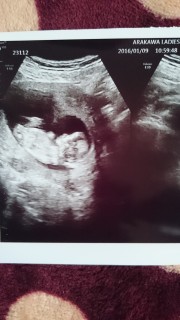

2週間前はガスの溜まり過ぎで腹部エコー出来なかったけど今回は無事見れた。 大きさは6cmで大きさも心拍も順調だそうです。 次の検診は4週間後。 長いなぁー(・・) 楽しみ♪

大きくなってましたー! 元気に跳ねていて、心音も初めて聞けました。 旦那さんも大喜びしてくれて成長してくれたベイビー に感謝です(∩´∀`∩)